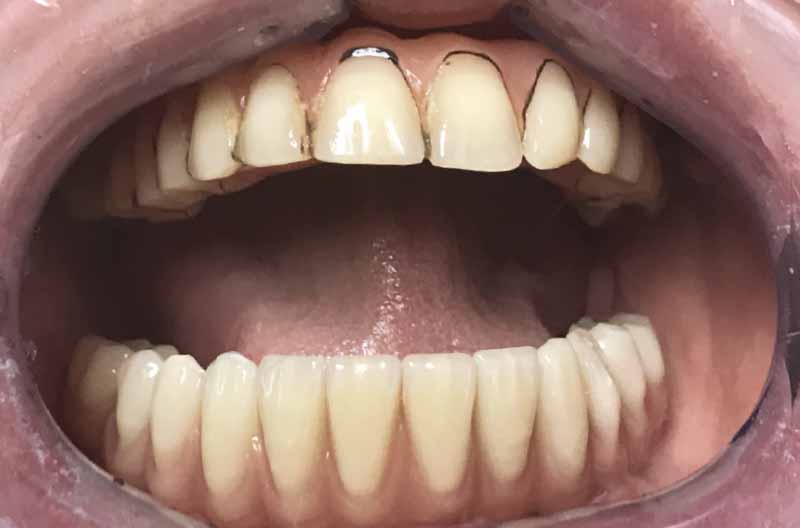

Viste le aspettative della paziente e la quantità di osso disponibile (Fig. 2) si propone come soluzione la tecnica All-on-Four. Il metodo All-on-Four consiste nel posizionare a livello mandibolare quattro impianti intraforaminali, di cui due nella zona degli incisivi laterali e due distali inclinati (“tiltati”) davanti ai forami mentonieri.

- Fig. 2